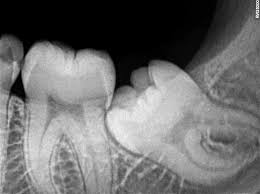

Wisdom teeth, also known as third molars, often become impacted or grow at angles that can cause pain, infection, or damage to adjacent teeth. Removal is typically recommended when there isn't enough space in the jaw for them to erupt properly or when they are causing clinical complications.

Wisdom teeth X-ray Wisdom tooth extraction procedure